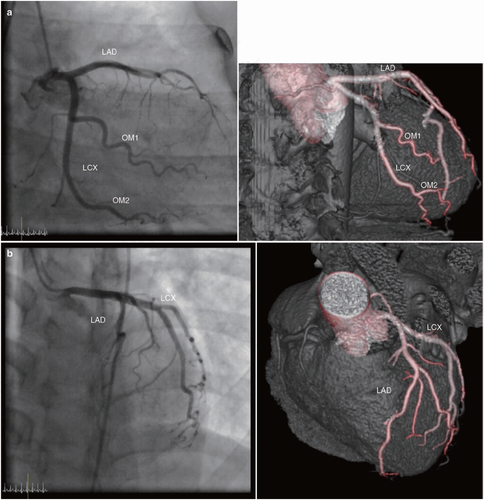

血管造影是通过向手臂留针的方法,打入一些造影剂,然后打完后进行ct或是x光检查,这时候不会有任何的疼痛,有疼痛也就是在打针的时候那一点针扎的疼痛,等到做完检查后就可以将这个针拔掉就可以了。

通过血管造影这个先进的检查方式,能够检测到x光没有办法检测到的疾病。血管造影这项检查项目会有一定的创伤,人们在做之前需要做好相应的准备工作。人们要按照医生嘱咐的注意事项来做,这样才可以保证结果的准确性。